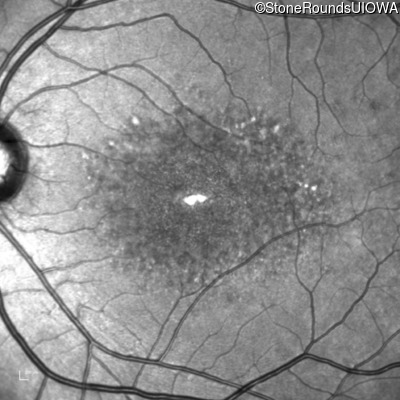

| Age at visit: 17 years |